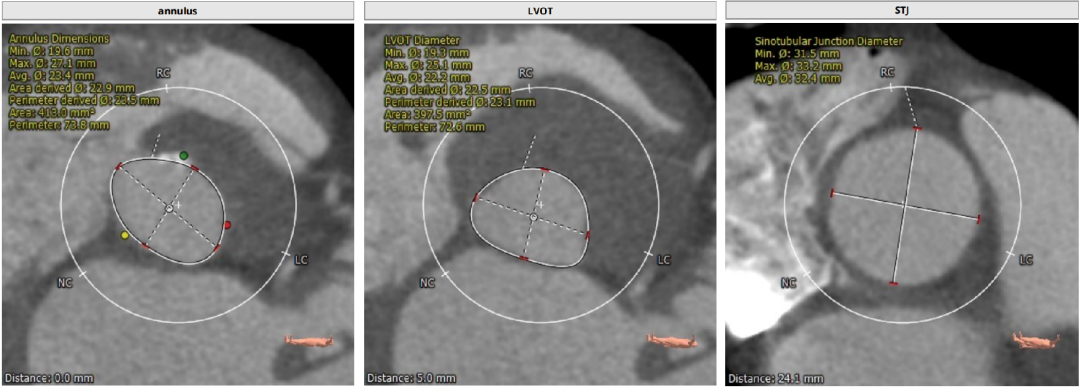

Annulus:23.5mm

LVOT:22.2mm

STJ 32.4mm

升主动脉:39.7mm

LM:11.8mm

RM:15.7mm

CT分析

Annulus:23.5,初选26/29瓣膜。LVOT短径19.3mm,STJ高度足够,宽度适中。

窦部空间足够,升主增宽,左右冠高度合适。

心脏角度不大,轻度钙化,左右窦黏粘;释放体位LAO 9、CRA 1;运用cusp-overlap技术定位角度;RAO17°、CAU 28° 。